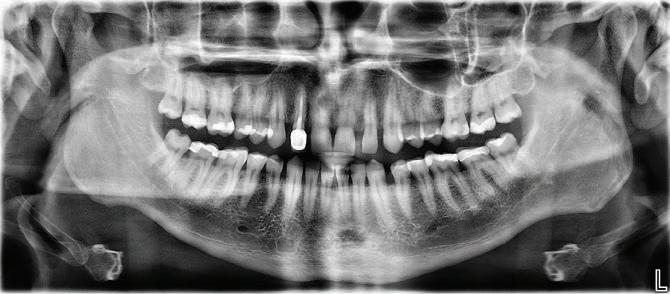

Dental Tribune Bulgarian Edition / октомври 2022 г.16 клиничен случай с алайнери Г орният латерален ре зец е вторият найчесто вродено липсващ зъб.1,2 Поради разполо жението му във видимата зона на усмивката лечение то на подобни случаи нала га мултидисциплинарен под ход, целящ отличен функцио нален и естетичен резултат. Налице са няколко лечебни мо далности, свързани с различ но разпределение на място то: първият вариант е орто донтско отваряне на място и възстановяване на липсва щия зъб с конструкция, под държана от съседните зъби3 или от имплант4, докато при втория подход разстоянията се затварят и премоларът заема мястото на канина.5 Изборът на лечебен подход трябва да бъде направен съв местно от зъболекар и паци ент въз основа на очакванията на последния и предвиди мостта на лечението. Множе ство фактори влияят върху това решение, като напри мер типа малоклузия, размера, формата и цвета на кучеш ките зъби6, оклузалните вза имоотношения (овърджет и овърбайт), лицевия профил, дължината на зъбната дъга и несъответствията в разме ра на зъбите.7 В настоящата публикация се разглежда случаят на жена в зряла възраст с вродена лип са на горен ляв латерален резец. Бяха приложени про зрачни алайнери за отваряне на място за единичен им плант и бяха постигна ти функционална оклузия и отлична естетика. ПРЕДСТАВЯНЕ НА СЛУЧАЯ Диагноза Пациентката бе на 32 годи ни, когато лечението започна, и първоначалното ѝ състоя ние бе следното (фиг. 1–3): липсващ горен ляв латерален резец; клас II, подклас I малоклузия; отклонение на горната сре динна линия вляво; Доклад на клиничен случай ЛЕЧЕНИЕ С АЛАЙНЕРИ НА ПАЦИЕНТ С АГЕНЕЗИЯ НА ЛАТЕРАЛЕН РЕЗЕЦ Д-р Iro Eleftheriadi и д-р Christodoulos Laspos, Гърция и Кипър Фиг. 1a–h Предоперативни лицеви и интраорални снимки. Фиг. 2a–e Дигитални модели преди началото на лечението. Фиг. 3 Панорамна снимка преди лечението. Фиг. 1a Фиг. 1d Фиг. 1f Фиг. 2a Фиг. 2d Фиг. 2b Фиг. 2e Фиг. 3 Фиг. 2c Фиг. 1b Фиг. 1e Фиг. 1g Фиг. 1h Фиг. 1c

Dental Tribune Bulgarian Edition / октомври 2022 г. 17клиничен случай с алайнери леко струпване в долната че люст; несъответствие по Болтън (мандибуларен излишък от 3.06 мм във фронталната зона и общо 1.47 мм); издължено лице с лицева аси метрия; конвексен профил с ретруди рана долна челюст и проми нентен нос. На мястото на зъб #46 бе на лице имплант, а зъби #16 и 26 са ендодонтски лекувани. Тези зъби бяха асимптоматич ни, затова бе взето решение да се прави релечение само при нужда. Мъдреците липсваха. Анализът на телерентгеногра фията (фиг. 4) показа ретрог натна мандибула (SNB: 74.2°) и нормална инклинация на резците както в

Dental Tribune Bulgarian Edition / октомври 2022 г.18 воначалния план. Тези пробле ми бяха адресирани чрез допъл нителна поръчка на алайнери с торк контрол и зададено екст рудиране на задните зъби с цел установяване на добри оклузал ни контакти в дисталните об ласти, като бяха предвидени и оптимизирани атачмънти с контрол над корените за корекция на ангулацията на макси ларните резци (фиг. 8). Резултати от лечението Панорамната рентгено графия след ортодонтското лечение показа благоприятна паралелна позиция на съседни те зъби, подходяща за поставя не на имплант в областта на #22, както и конвергенция на ко рените на зъби #44 и 45 (фиг. 9), но преценихме, че няма да от деляме допълнително лечебно време за коригирането ѝ поради факта, че пациентката бе мно го доволна от постигнатия до момента резултат. След при ключване на лечението бяха постигнати отлични взаимо отношения клас I при мола рите и канините, а срединни

съвпадаха. Върху им